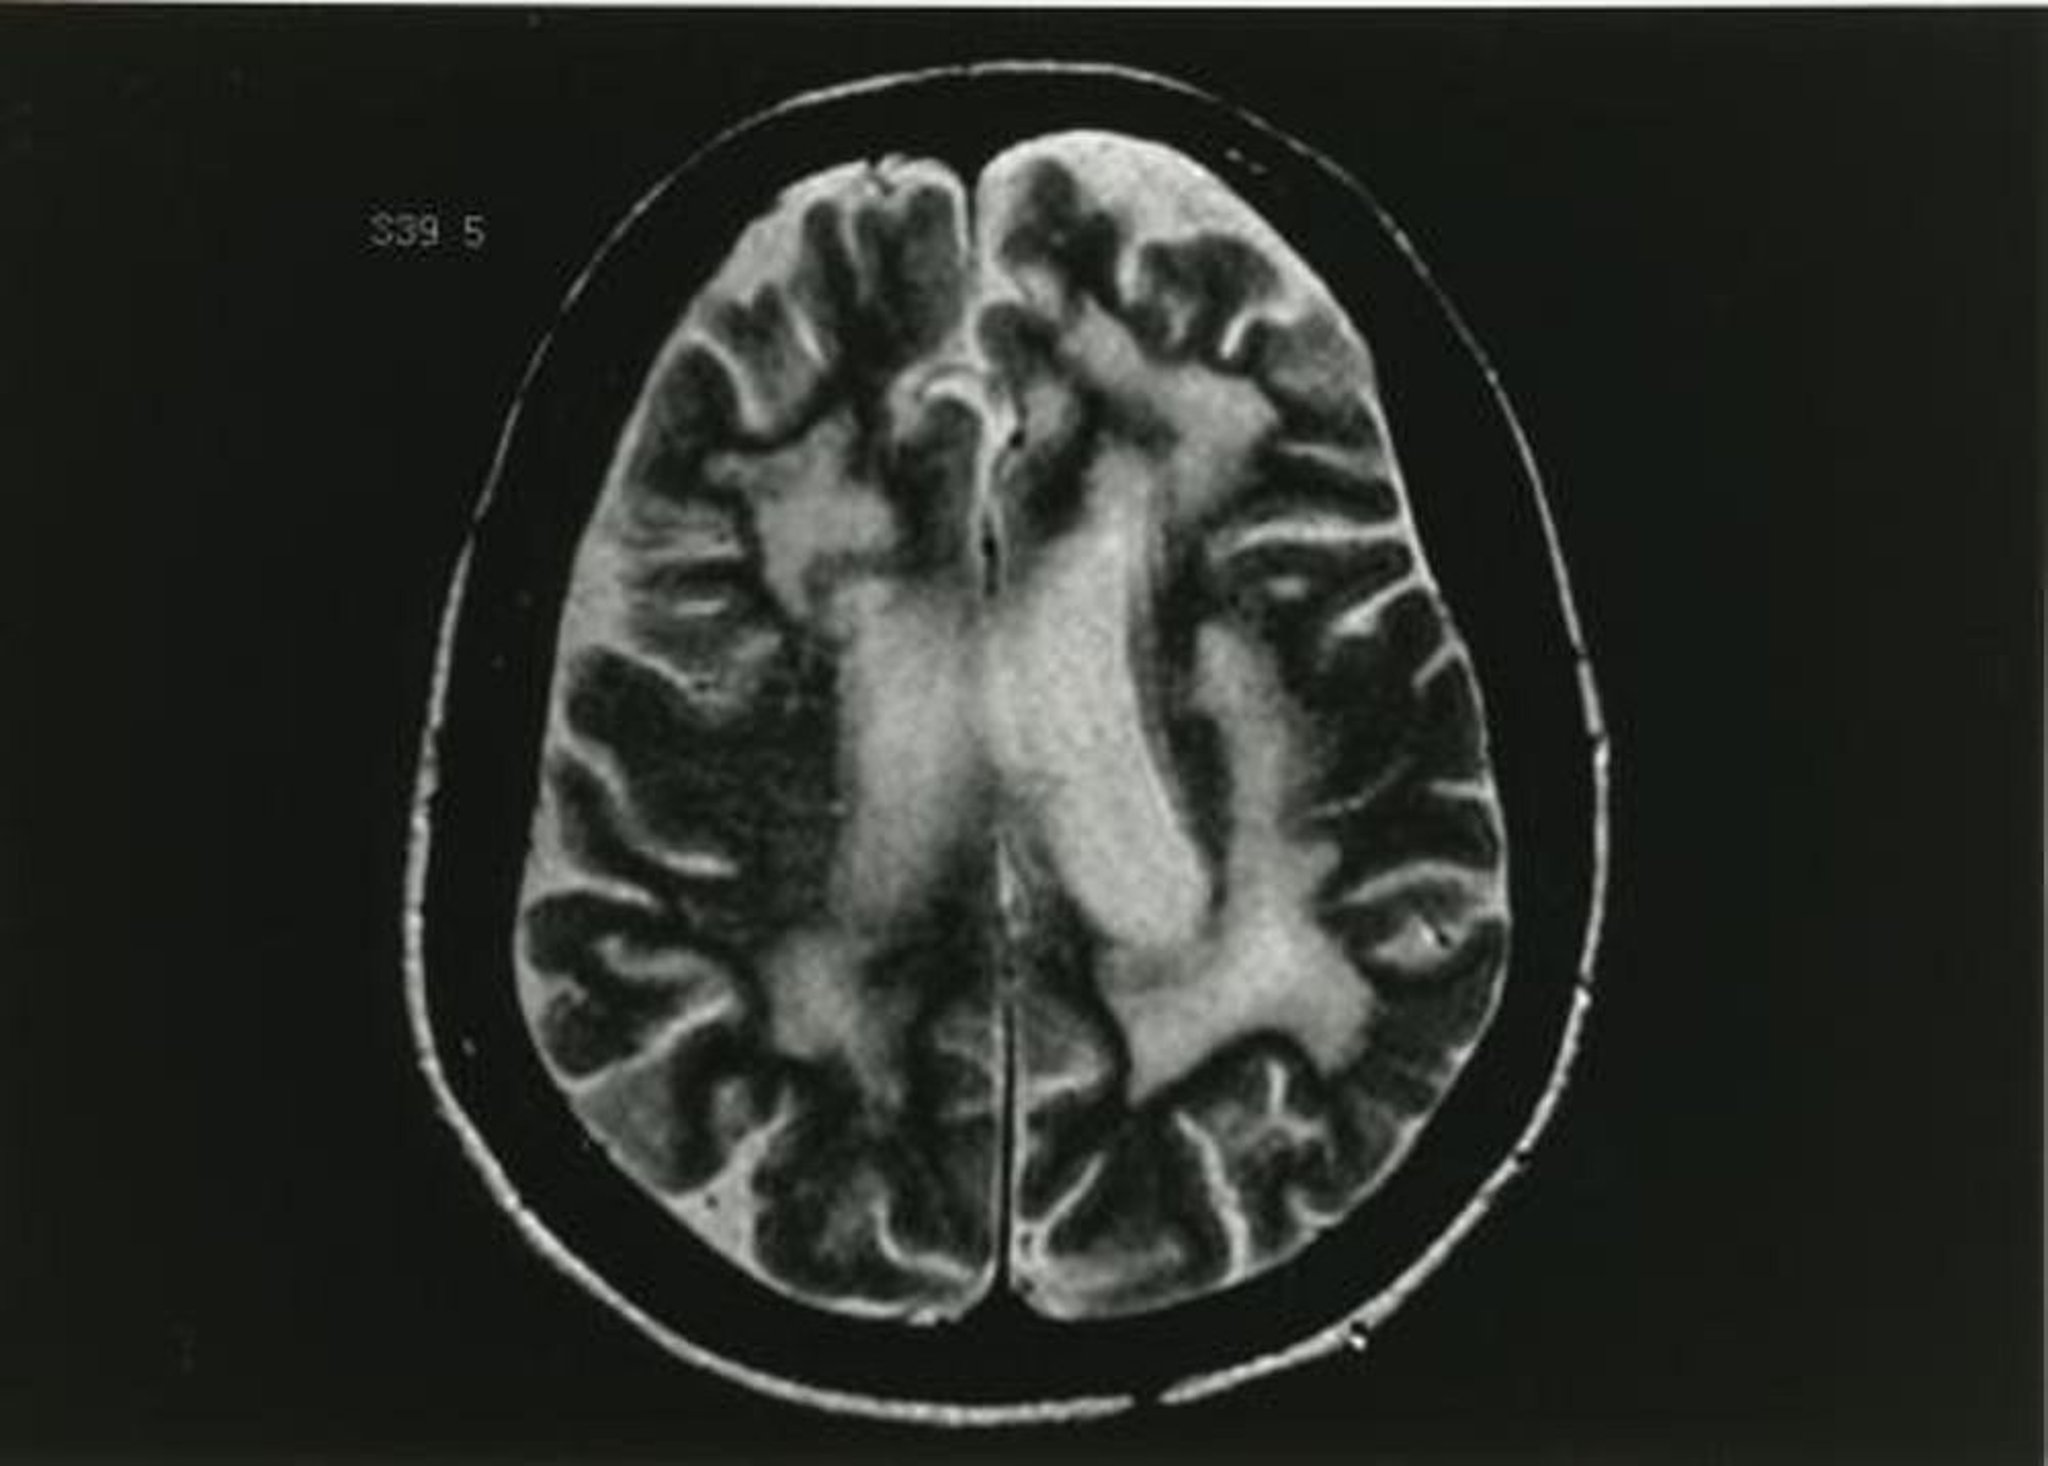

Progressive Multifokale Leukoenzephalopathie (PML)

Dieses T2-gewichtete MRT-Bild zeigt mehrere Veränderungen der weißen Substanz.

Abbildung zur Verfügung gestellt von John E. Greenlee, MD.